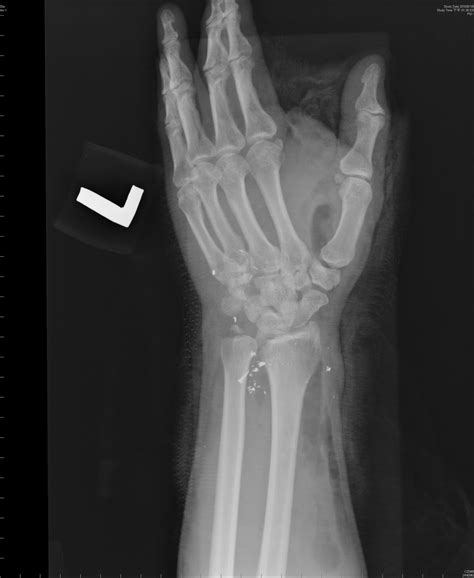

Fractures of the Styloid Process Ulna are relatively rare but can occur due to trauma, such as a fall on an outstretched hand or a direct blow to the wrist. These fractures can be challenging to diagnose due to their small size and the overlap of other bony structures on radiographs. However, they can cause significant pain and instability in the wrist joint.

Imaging studies, such as X-rays, CT scans, and MRI, can provide detailed information about the Styloid Process Ulna and surrounding structures. These studies can help identify fractures, degenerative changes, and other abnormalities.